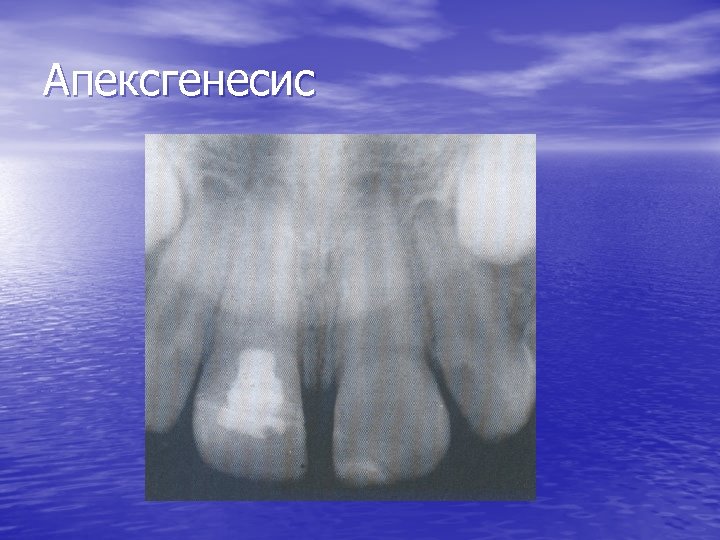

Апексгенезис 1. Ниска пулпотомия 2. Висока пулпектомия

Апексгенесис

Постигане на апексгенесис